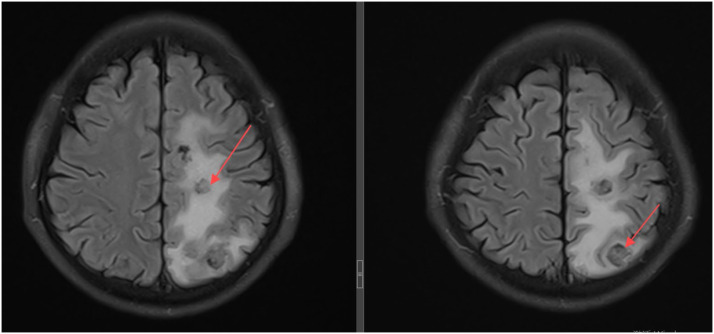

Disseminated TB with central nervous system involvement.

弥散性结核伴中枢神经系统受累。